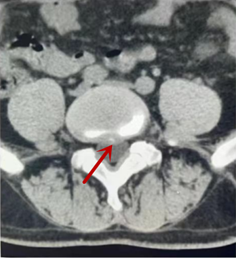

CT利用X射線對人體檢查部位通過電腦切成若干層掃描,然后把每層的圖像都能顯示出來。CT相對于X光片具有更高的密度分辨力,可直接顯示X線片無法顯示的病變,觀察腰椎有無微小的骨折、骨質(zhì)有無破壞等骨質(zhì)情況、以及腰椎間盤突出、腰椎神經(jīng)根、椎管、椎間小關(guān)節(jié)的情況等。同時還可以通過后處理,重建腰椎矢狀位或冠狀位圖像,形成腰椎的3D圖像,更直觀地觀察病變部位,對腰椎手術(shù)風(fēng)險具有提示作用,對手術(shù)方式的選擇具有指導(dǎo)意義,但是對神經(jīng)、脊髓損傷程度的顯示不如MRI,軟組織的分辨率仍有一定限制,對椎管內(nèi)病變顯示欠佳,且有一定的輻射。

箭頭提示椎間盤突出